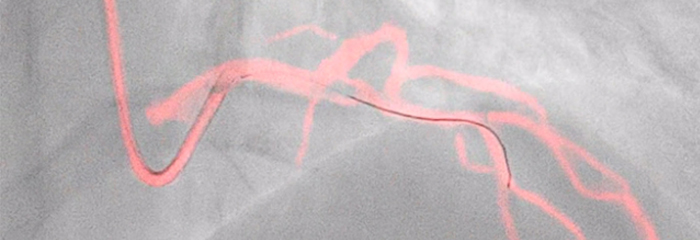

A medida que se considera la posibilidad de someter a más pacientes con coronariopatías a tratamientos intervencionistas mínimamente invasivos, la planificación de los mismos se ve obstaculizada por las limitaciones de la angiografía coronaria en 2D para detectar y evaluar la estenosis coronaria. Los datos no están conectados de manera coherente y significativa antes y durante el procedimiento, lo que añade tiempo y complejidad a la planificación del tratamiento. Hemos diseñado nuestras soluciones de cardiología de modo que pueda obtener las ventajas de la eficacia clínica en el laboratorio de cateterismo:

La terapia guiada por imagen, iFR, los ultrasonidos intravasculares y la monitorización hemodinámica, así como la planificación previa al procedimiento cardiaco y las aplicaciones avanzadas, están conectados a la interfaz de la terapia guiada por imagen para permitir la visualización, manipulación y configuración personalizada en el monitor desde un único módulo de control en mesa o desde la sala de control.